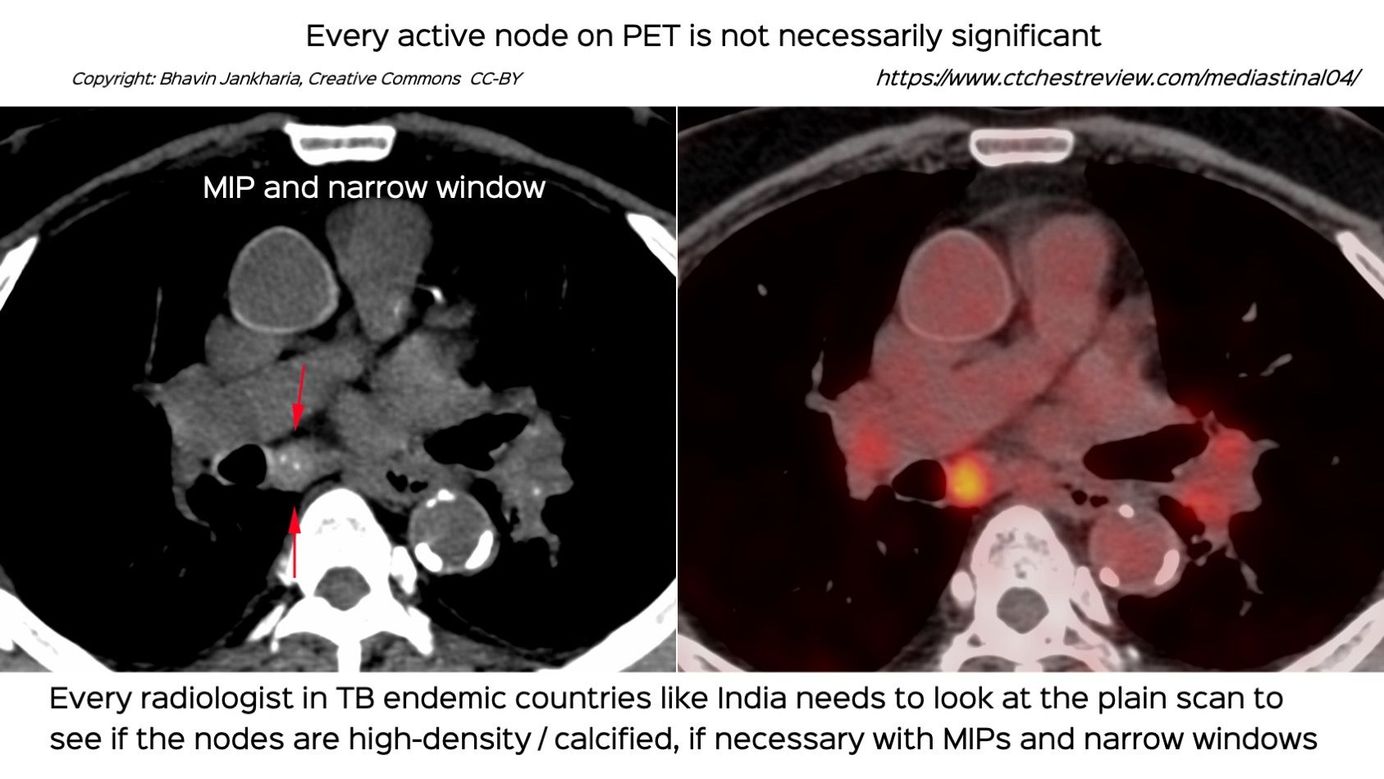

Case 33: Every Active Lymph Node on PET is Not Necessarily Significant Paid Members Public

Every active node on PET is not necessarily significant and needs to be evaluated for calcification / high density - features that suggest old healed disease